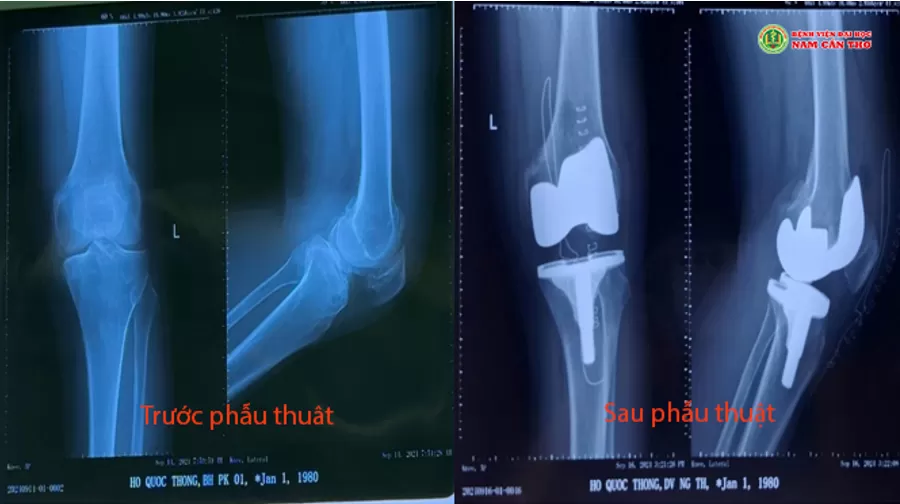

☘ Qua quá trình thăm khám kỹ càng, làm các cận lâm sàng cần thiết. Các bác sĩ kết luận bệnh nhân thoái hóa khớp gối trái, giai đoạn IV, được chỉ định phẫu thuật thay khớp gối toàn phần. Kỹ thuật này thay thế các phần sụn khớp gối bị tổn thương bằng một bộ phận khớp nhân tạo.

☘ Sau 2 giờ, ca phẫu thuật bởi Bs CKI Nguyễn Huỳnh Quang Huy, Ths.Bs.Thái Công Toàn Em, Bs. Nguyễn Quang Vinh, Bs Trần Thanh Trọng cùng ê kip thực hiện thành công. Sau phẫu thuật bệnh nhân tỉnh, vận động tập đi lại từ từ và được xuất viện tái khám định kỳ theo chỉ định của bác sĩ.